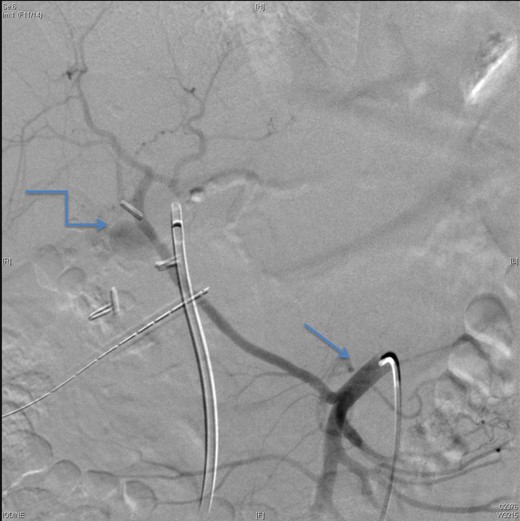

On Day 7, the patient bled again from the same aneurysm of the left hepatic artery. A repeated angiography revealed the bleeding with a reduced flow in the stented, replaced right hepatic artery (Fig. 4). The active bleeding was stopped using gel-foam embolization of the two branches of the left hepatic artery (Fig. 5) with a decision to embolize the whole left hepatic artery if bleeding did not stop while holding the heparin infusion. The patient's liver function was preserved, and the bleeding stopped despite anticoagulation.

An angiographic scan showed reduced flow in the stented replaced right hepatic artery.